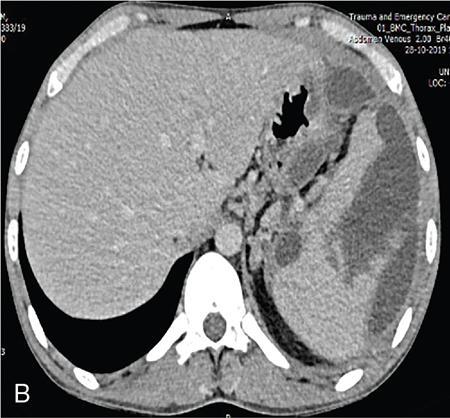

Vijay Kumar K.R. CONGENITAL SPLENIC ABNORMALITIES A multitude of variants and pathologies affect the spleen and it is pertinent for a radiologist to be aware of the common imaging appearances of the same. The spleen begins to develop in the fifth week of gestation from a mass of mesenchymal cells that condense between the two leaves of the dorsal mesogastrium. Several such aggregates fuse to form the lobulated embryonic spleen. The spleen is translocated to the upper left side of the abdominal cavity due to rotation of the stomach and differential growth of the dorsal mesogastrium. The mesogastrium fuses with the peritoneum over the left kidney and forms the splenorenal ligament. The lienorenal ligament fuses dorsally and the splenic artery courses behind the peritoneum as it enters the splenorenal ligament. The portion of dorsal mesentery between the stomach and spleen forms gastrosplenic ligament. Differentiated mesenchymal cells form the parenchyma, connective tissue and capsule of the spleen. The foetal spleen shows lobulations, which normally disappear before birth. However, they may persist along the medial part of the spleen. Sometimes a persisting portion of the spleen may extend medially and anteriorly over the upper pole of the left kidney. It may be mistaken for a space-occupying lesion arising from the kidney. Rarely it may extend posterior to the upper pole of the left kidney, displacing it anteriorly (Fig. 9.22.1.1). The notches and clefts along the superior borders are vestiges of the grooves that initially separated the foetal lobules. They may be 2–3 cm deep. They may mimic a splenic laceration in a patient with abdominal trauma, and the embedded peritoneum at the waist may simulate splenic infarction or haematoma. Hence caution should be exercised. A normal spleen which does not have a fixed ligamentous attachment can change position within the abdomen and is hence known as a wandering spleen. The spleen is normally anchored by the gastrosplenic and lienorenal ligament. Absence or weakness of one or more ligaments that affix the spleen. The spleen with its vascular pedicle as the sole attachment can become a hypermobile intraperitoneal organ. Rarely, the spleen may be normal in position with a wandering accessory spleen. Pregnancy (due to hormonal effects), prune belly syndrome, splenic cysts, malaria, Hodgkin’s disease and lymphangioma. Some of the affected patients may be asymptomatic and diagnosis may be incidental. Clinically it presents as a mobile, palpable, notched mass. Pressure on the vascular pedicle or torsion causes symptoms such as acute abdominal pain, nausea and vomiting. Torsion involving the tail of the pancreas may present as pancreatitis. Confirms the absence of spleen in the left upper quadrant of abdomen with identification of splenic tissue at an ectopic site. Power Doppler, colour Doppler and duplex sonography allow for the identification of blood flow in the splenic vessels and parenchyma. Intermittent torsion may be responsible for an enlarged spleen. Pathognomonic feature of wandering spleen is absence of the spleen in the upper abdominal cavity and presence of a well-demarcated, homogeneously enhancing mass of soft tissue in the pelvis or abdomen. Sometimes a wandering accessory spleen can be visualized as a long vascular pedicle connecting a small mass to the splenic vessels (‘jokari sign’). It can locate ectopic splenic tissue and can also indicate the viability of the tissue. Splenic vessel anatomy can be well demonstrated. 99mTc-sulphur colloid scintigraphy and heat denatured 99mTc-labelled red blood cell imaging provide useful information regarding size and location of splenic tissue. Torsion is indicated by lack of tracer activity in a previously demonstrated wandering spleen. Twisting and torsion of splenic artery can be demonstrated by celiac arteriography. The venous phase may demonstrate splenic vein obstruction with collateral circulation and varices. A congenital focus of normal splenic tissue that is separate from the main body of the spleen is known as an accessory spleen. It results from the failure of fusion of some embryonic splenic buds within the dorsal mesogastrium. Its incidence varies from 10% to 30% on autopsy examinations. They vary from a few millimetres to several centimetres in diameter. They most commonly are found around the splenic hilum. The second most common location is the pancreatic tail. They can also be found in the stomach wall, omentum, mesentery, large bowel and scrotum. Reveals a round or oval mass of tissue around the splenic hilum that is isoechoic with the main spleen. On noncontrast images they are isodense to the main spleen. CECT reveals serpiginous enhancement on arterial phase followed by homogeneous enhancement on venous phase-like spleen (Fig. 9.22.1.2). Accessory spleen is mildly hypointense to the spleen on T1 images and isointense on T2 images. Contrast administration reveals enhancement similar to that of spleen on the arterial, portal and late phases. It is isointense to spleen on DWI images with similar ADC values. 99mTc-sulphur colloid scintigraphy and heat denatured 99mTc-labelled red blood cell imaging show functional uptake in splenic tissue and differentiate splenule from other masses. PET CT-FDG avid mass can mimic tumour. Surgical resection is the preferred mode of treatment in the background of hypersplenism or lymphoma. It is characterized by an ectopic splenic tissue or an abnormal connection between the gonad and the spleen. The left side is more commonly involved than the right side. The accepted theory is that splenic gonadal fusion occurs due to abnormal attachment of the splenic anlage in the left dorsal mesogastrium with the left urogenital fold, during the fifth to eighth weeks of gestation. It has a higher male preponderance and can interfere with left testicular descent and closure of processus vaginalis. It commonly presents as inguinal hernia and cryptorchidism. The spleen and gonad are attached by a fibrous or splenic cord across the peritoneal cavity. It is associated with limb defect syndrome, cleft palate, micrognathia, anal anomalies, craniosynostosis, spina bifida, cardiac malformations, thoracic malformations and diaphragmatic hernias. This is not associated with congenital anomalies. Shows a well-defined scrotal mass with echotexture similar to that of spleen. Confirms splenic tissue in inguinal or scrotal area. It is characterized by the absence of spleen with duplication of right-sided structures. (Right isomerism). It has a slight male preponderance with an incidence of 1 in 40,000 live births. It has a poor prognosis due to its high association with congenital cardiac abnormalities (Fig. 9.22.1.3). It is of uncertain aetiology, and maybe associated with the mutations of CFC1 gene, SHROOM3 gene etc. Delayed development of embryonic curvature can be another cause. It is also theorized that it can be caused due to vascular compromise by pressure on splenic blood supply from adjacent structures. Splenectomy – Usually has a surgical history and is not accompanied by associated anomalies. It is a heterotaxy syndrome associated with multiple spleens and duplication of left-sided structures. (Left isomerism). It has an equal gender predilection with a slightly higher female preponderance. It has a fairly better prognosis than asplenia and is associated with a lesser incidence of cardiovascular anomalies (Fig. 9.22.1.4). It is of uncertain aetiology, and maybe associated with the mutations of CFC1 gene, SHROOM3 gene etc. Accelerated development of embryonic curvature can be another cause. SPLENIC INFECTION AND ABSCESS The infection of the spleen can show three patterns. Fungal and granulomatous infections usually present with multiple micronodules. A pyogenic abscess usually manifest as a solitary lesion. Imaging of diseases causing splenic nodules is never the sole basis for diagnosis. The clinical presentation and laboratory testing (tumour markers, tuberculosis testing and bone marrow biopsy) help in establishing an accurate diagnosis. The imaging findings are nonspecific and the nodules may vary in size from a few millimetres up to 2 cm in diameter. They maybe hypoechoic on ultrasound and hypoattenuating on CT. They are of low signal intensity on T1-weighted sequences and vary from hypointense to hyperintense on the T2-weighted sequences. The nodules show no enhancement or show ring enhancement after contrast study. Healed granulomas are seen as scattered, discrete, small calcifications in an otherwise normal spleen. With increasing number of immunocompromised patients, such as oncology patients undergoing aggressive chemotherapy, critically ill patients in intensive care units, injection drug abusers, and HIV-infected patients, there is rise in the incidence of splenic abscess. For splenic abscess to develop, it may require the presence of bacteremia (sepsis and septic emboli) and altered splenic architecture, which is caused secondary to a haematoma, infarct, or sickle cell disease. Abscesses can also develop from the extension of infection from adjacent organs, like in cases of infected pancreatitis and perinephric abscess, which are less common. In about 20% of cases, cause or source could not be discovered. Abscesses can be unilocular or multilocular, solitary or multiple, depending on the causative organisms and patient’s immunity. Mortality ranges from 15% in otherwise healthy patients with unilocular splenic abscess to 80% in immunocompromised patients with multiple abscesses. Abscesses which are multilocular, gas-containing or due to gram-negative bacillus show poor prognosis. A pyogenic abscess is usually solitary, unilocular/multilocular, but it can also be multifocal. These are uncommon and are reported in 0.14%–0.70% of large autopsy series. Most common presentation is fever (92%), left upper abdominal pain (77%) and leucocytosis (66%). Other symptoms are left pleural effusion and splenomegaly. It can be solitary or multiple, unilocular or multilocular. The appearance of splenic abscess depends on the stage of development. In the early stages of the disease, an abscess appears as an ill-defined mass later developing into a complex collection with septations, debris and sometimes gas. In later stages, after a capsule is developed, the lesion becomes well defined. Left pleural effusion is seen in around 42% of cases. Left lung base atelectasis in 20% of cases and splenomegaly is seen. Abscess with air can be identified based on the presence of extraluminal gas or air–fluid levels in the left upper quadrant. Ultrasonography has a sensitivity of 75%–98% in detecting splenic abscess. This is a very useful modality in patients who are bedridden, with renal impairment and for assessment of small splenic lesions (Fig. 9.22.2.1). Ill-defined hypoechoic mass mimicking a mass is seen in the early phase of the infection and a complex mass with internal septations, debris, rarely acoustic shadowing caused by gas is seen in later stages. The capsule appears as a thin hyperechoic rim. It is noninvasive, speedy, and a modality with high sensitivity (92%–98%). It helps in differentiating unilocular from multilocular lesions and, gives exact anatomical localization and information about perisplenic area, which later helps in planning-guided management procedures. An abscess is seen as a hypodense collection or complex cystic lesion with enhancing rim on the postcontrast study (Fig. 9.22.2.2). CT may help in identifying concurrent areas of infection and, thus, the source of infection. On CT, an abscess may look similar to an infarct, haematoma, or neoplasm. An infarct lacks mass effect, unlike abscess or tumour (Fig. 9.22.2.3). The presence of gas within the lesion is diagnostic of abscess; however, this finding is rare. Splenic abscesses show low signal on T1-weighted images and high signal on T2-weighted images compared with the normal spleen. Minimal to intense peripheral enhancement is seen after IV administration of gadolinium. But MRI is not routinely done, as many patients are clinically unstable. This plays a limited role in the detection and localization of splenic abscess. A nonspecific filling defect is seen on a 99mTc-sulphur colloid scan within spleen if the size is more than 2 cm in diameter. Normal inherent splenic activity on 67Ga scans and 111In-labelled leukocytes scans obscures any kind of inflammatory focus in the spleen, giving rise to false-negative examination. 67Ga scans are nonspecific as tracer uptake can be seen in neoplastic conditions such as lymphoma. Detection and characterization of the abscess are better done if 99mTc-sulphur colloid scan is done prior to 111In-labelled leukocytes scan. FDG PET/CT can also detect the site of infection but not used in the diagnosis of splenic abscess. Early diagnosis of an abscess is prompted for a better outcome. Based on laboratory findings, appropriate antibiotic therapy initiated. USG or CT-guided percutaneous aspiration is tried if the abscess is less than 5 cm in size, and for larger abscesses, percutaneous drainage procedures are done preserving the spleen. Splenectomy is reserved for complicated infections. Fungal abscesses are usually seen in immunocompromised patients with neutropenia such as patients with acquired immunodeficiency syndrome (AIDS), on chemotherapy and immune suppressive agents, and with lymphoproliferative disorders. With the advent of aggressive chemotherapy, the incidence of splenic fungal infections has increased. Approximately 7% of patients with acute leukaemia have hepatosplenic fungal infections. Multiple microabscesses are common. Hepatosplenic candidiasis lesions are very small, and before the advent of CT and MRI, their detection was too difficult. They measure in the range of 5–10 mm in diameter; however, they may be even miliary (<5 mm). Infections are mostly caused by candida species. Other organisms are aspergillus, Histoplasma and Cryptococcus. Imaging characteristics depend on the stage and severity of neutropenia. In cases of chronic disseminated infections with poor neutrophil counts, sometimes lesions are not visible as the host fails to produce an immune response. Lesions become apparent once neutrophil counts improve. Patients presenting with fever and splenomegaly are not improving on conventional antibiotic therapy, and with associated immunocompromised status, fungal infections are to be considered. No single imaging is specific or sensitive in establishing the diagnosis. Serial imaging is needed to detect hepatosplenic involvement; however, tissue diagnosis is the gold standard. Four different patterns are seen in hepatic candidiasis. Multiple, small, homogeneous hypoechoic nodules are the most common finding. Less commonly wheel-within-a-wheel appearance (i.e. the target sign) is seen in the early stage of infection. The first wheel is the peripheral hypoechoic zone of fibrosis and an echogenic second wheel of inflammatory cells around a central hypoechoic nidus containing necrosis and fungal elements. Later these lesions evolve into Bull’s eye lesion where there is a central echogenic focus surrounded by a hypoechoic halo. Lesions become small and hyperechoic with various degrees of posterior acoustic shadowing, with or without calcification, or they may even disappear later in the course of the infection. Splenic nodules are hypodense lesions measuring in the range of 5–10 mm. Only 30% of cases are detected in noncontrast studies. They often have low attenuation, although there can be a focus of high attenuation or a ‘wheel-within-a-wheel’ pattern. Peripheral ring of enhancement is noted in around 70% of cases in the arterial phase of CT, and it is said to disappear on the portal venous phase. There is no significant difference in the detection of the lesions between arterial and portal venous phases of contrast studies. MRI is said to be the investigation of choice for diagnosis of hepatosplenic candidiasis and is superior to CT and USG, especially when short-time inversion recovery sequence is used. MR imaging is also used to monitor the response to antifungal therapy. Based on MRI findings different phases of hepatosplenic candidiasis are described. Lesions are small, measuring less than 1 cm in diameter. They show mildly hypointense on the T1-weighted images and markedly hyperintense on the T2-weighted images. In 2 weeks to 3 months, acute lesions are transformed into subacute lesions. The lesions reveal mildly increased signal on both T1- and T2-weighted sequences. On all sequences, a peripheral ring of very low signal intensity is seen. Following the gadolinium administration, the central region of the lesions show enhancement; however, the peripheral ring continues to have low signal intensity, making them more obvious. It takes from 3 months to more than 1 year for the healed fungal foci composed of fibrous tissue of differing densities and degrees of vascularization to appear on MRI. The lesions measure 1–3 cm, become irregular, and the central area disappears. Chronic healed fungal abscesses have low signal intensity on T1-weighted images and are isointense to mildly hyperintense on T2-weighted images. No perilesional dark ring is noted. These lesions are moderately hypointense on early postgadolinium images and minimally hypointense on delayed postgadolinium images. Mycobacterial tuberculosis infections are mainly seen in immunocompromised patients. Spleen involvement is seen in disseminated, miliary infection in about 80%–100% of autopsy cases; however, it is documented less on imaging. Splenic tuberculosis is seen in the form of nodules measuring ∼ 0.2 and 1 cm in diameter. The macronodular form is very rare (Fig. 9.22.2.4). Hypoechoic pattern is seen. Hypoattenuating nodules with lymphadenopathy noted. Depending on the different stages of the tubercular process, intensities on T1- and T2-weighted images vary. On contrast-enhanced T1-weighted images, lesions most often show peripheral enhancement less commonly gradual peripheral enhancement with complete filling is noted. It is also called as Mycobacterium intracellulare infections. These are also typically seen in immunocompromised patients. Splenomegaly with multiple, low attenuation nodules is seen. Associated findings such as hepatosplenomegaly, diffuse jejunal wall thickening and enlarged lymph nodes are seen. Lymph nodal involvement is homogeneous as opposed to Mycobacterium tuberculosis infections. Focal splenic or hepatic lesions are noted in about 30% of patients with HIV who are infected with M. tuberculosis but are rarely noted in those infected with M. avium intracellulare. Marked splenomegaly is more common in M. avium intracellulare than in M. tuberculosis infection. It is a common opportunistic infection in patients with HIV. Extra pulmonary involvement manifested in the form of necrotizing granulomas. Spleen involvement is an incidental finding. When treated the nodules may enlarge and become progressively calcified in a rim like or punctate fashion. Disseminated infection can show punctate calcification in adrenal glands, pleural or peritoneal effusions, that subsequently calcify. Splenomegaly with small hypoechoic lesions with cystic components or tiny, highly reflective, nonshadowing foci or calcified granulomas. The nodules are hypodense. Calcified granulomas are seen in later stages. This is a self-limited disease caused by bartonellae henselae. Hepatosplenic involvement is rare. This disease is to be considered when a patient presents with abdominal pain, fever of unknown origin, and multiple hypodense lesions in the liver and spleen. It is also called as echinococcosis, a disease seen in endemic regions and in patients emigrated from endemic areas. The causative organism is a zoonotic tapeworm echinococcus granulosus. The most commonly involved organs are the liver, lung, peritoneum, kidney, brain, mediastinum and heart. Spleen is rarely primarily involved. Spleen is involved in approximately 2% of cases of abdominal hydatidosis. Spleen involvement is seen in case of an extensive abdominal hydatidosis, like after the rupture of liver hydatid cyst or in cases of systemic dissemination of infection. Larvae of the tapeworm incite an inflammatory response after its entry into the target tissue in the host where it forms a hydatid cysts consisting of three layers. Peri cyst is an outer layer of modified host cells forming a dense and fibrous layer. The middle layer laminated layer and an inner germinal layer made up of daughter cysts, also called as brood capsules. Scolices develop in the brood capsules. The laminated and germinal layer forms the true cyst wall. After the parasites die, the cysts become inactive, may calcify, and undergo fibrosis. Patients present with abdominal pain, splenomegaly and fever. The diagnosis is to be suspected in all patients from endemic areas presenting with a splenic cyst. A World Health Organization Working Group on echinococcosis has a standardized sonographic classification of echinococcal cysts (Table 9.22.2.1). CE, cysticechinococcosis; CL, undifferentiated simple cystic lesions. Radiological appearances depend on the natural aging process of the cyst. Classic imaging characteristics are lost when the cyst becomes secondarily infected. A ring-like or curvilinear calcification noted in the left hypochondriac region. This may represent the calcification of pericyst in later stages of the disease. Ultrasound is an easy and most commonly used for evaluation of a suspected case of abdominal echinococcal disease. It is used for the diagnosis, planning the management and follow-up. Shifting of brood capsules within the cyst causes fine internal echoes, that is ‘The snowflake sign’ (hydatid sand). Detached laminated endocysts may be seen within the cysts, that is ‘The. Waterlily sign’. Mother cysts may be partially /completely filled by daughter cysts. Calcifications with posterior acoustic shadowing are seen in later stages of the disease. CT and MRI are indicated for widespread disease and complications and for planning percutaneous therapy and surgery. Complications of a hydatid cyst include compression of the adjacent structures, cyst rupture, secondary infections, anaphylaxis and fistulization to surrounding structures. A hydatid cyst may be seen as a well-defined, hypoattenuating cystic lesion with fluid-attenuation values and a distinguishable wall. CT is more sensitive for subtle wall calcification. May appear hyperdense because of debris, hydatid sand and inflammatory cells (Fig. 9.22.2.5). In CE 2 cysts, peripherally arranged daughter cysts, completely fill them other cyst. The daughter cysts show lower attenuation than the mother cyst. Type CE 3 lesions are round or oval with occasional calcification and daughter cysts. They usually show high attenuation. Type CE 4 cysts are complex masses. Intravenous contrast administration reveals enhancement of septa and cyst wall. Type CE 5 cysts are complex cystic or solid-looking lesions, and they can be partially or completely calcified. The simple cysts show low signal on the T1-weighted images and markedly hyperintense on the T2-weighted images. The rim sign which is a low signal intensity rim well seen in T2-weighted MRI images is characteristic of hydatid disease. Enhancement of septa and cyst wall is noted after the intravenous administration of gadolinium. On T1- and T2-weighted images, the maternal matrix appears hyperintense relative to the daughter cysts. The collapsed parasitic membranes may show serpent sign or snake sign, which are hypointense on all sequences. Hypointensity on T1- and T2-weighted images are seen in type CE 4 and CE 5 cysts. The imaging findings combined with the clinical, immunologic testing and epidemiologic results, usually provide the correct diagnosis. Seen in cases of tuberculosis, histoplasmosis, less commonly in Pneumocystis jirovecii pneumonia and brucellosis. These are incidental findings usually preceded by hypoattenuating microabscesses. Microabscesses heal with or without preceding regression. More than five calcifications usually represent histoplasmosis, whereas less than five represent tuberculosis. A ring-like calcification is seen in Pneumocystis carinii pneumonia. Any granulomatous infection is more likely to involve other organs such as the liver, kidneys and lymph nodes. Hydatid cysts can show ring-like or curvilinear calcification (Fig. 9.22.2.6). SPLENOMEGALY AND HYPERSPLENISM Splenomegaly is often a nonspecific finding, and there are many causes for splenomegaly. The spleen can grow into large sizes towards right iliac fossa, crossing midline. On average adult spleen measures <11 cm in length,<7 cm wide,<5 cm thick, and weighs approximately 150 g (80–300 g). The size and weight of the spleen decrease with advancing age. Spleen size is significantly influenced by the sex and body height of an individual. Chow et al. assessed 1230 healthy volunteers and found that spleen length and volume were significantly and independently associated with sex, body height and weight. Taller and heavier male individuals have larger and longer spleens. In one study the spleen length in 6% of women, and 26% of men exceeded a strict upper limit of normal of 12 cm. Rosenberg et al. established an upper limit of standard splenic length of 12 cm for girls and 13 cm for boys (≥15 years). Massive splenomegaly is defined as a spleen size greater than 18 cm, is less common and includes haematological disorders and infections (Table 9.22.3.1).